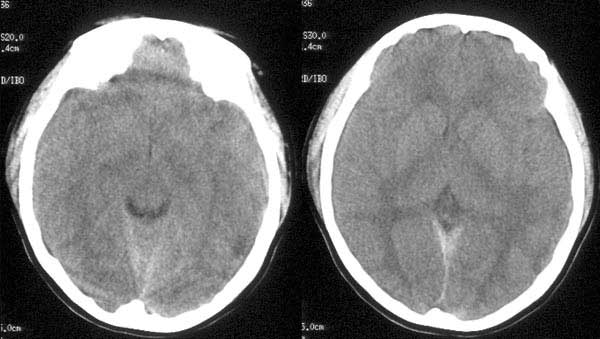

女性,18岁。车祸致伤头部3小时。

ct平扫:左颞骨内板下见细线形高密度出血影,左侧侧脑室受压变窄,中线结构向右侧移位。大脑镰、小脑幕及左枕部脑沟密度增高。鞍上池、环池均显示不清。

ct诊断:1、左颞硬膜下血肿。

2、蛛网膜下腔出血。

3、脑肿胀。